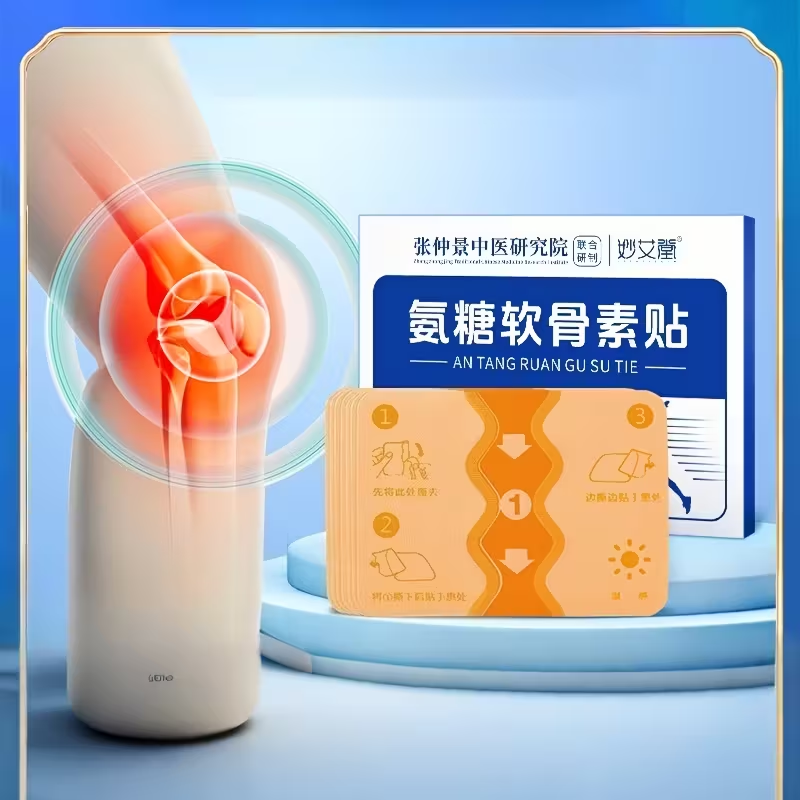

A solução em forma de adesivos terapêuticos avançados

Adesivos ósseo DR Mtsui Alivio de dores imediato

Esses adesivos são aplicados diretamente na região da dor

Eles utilizam:

✔ Tecnologia de liberação gradual

✔ Ativos naturais amplamente usados no MUNDO

✔ Ação local prolongada